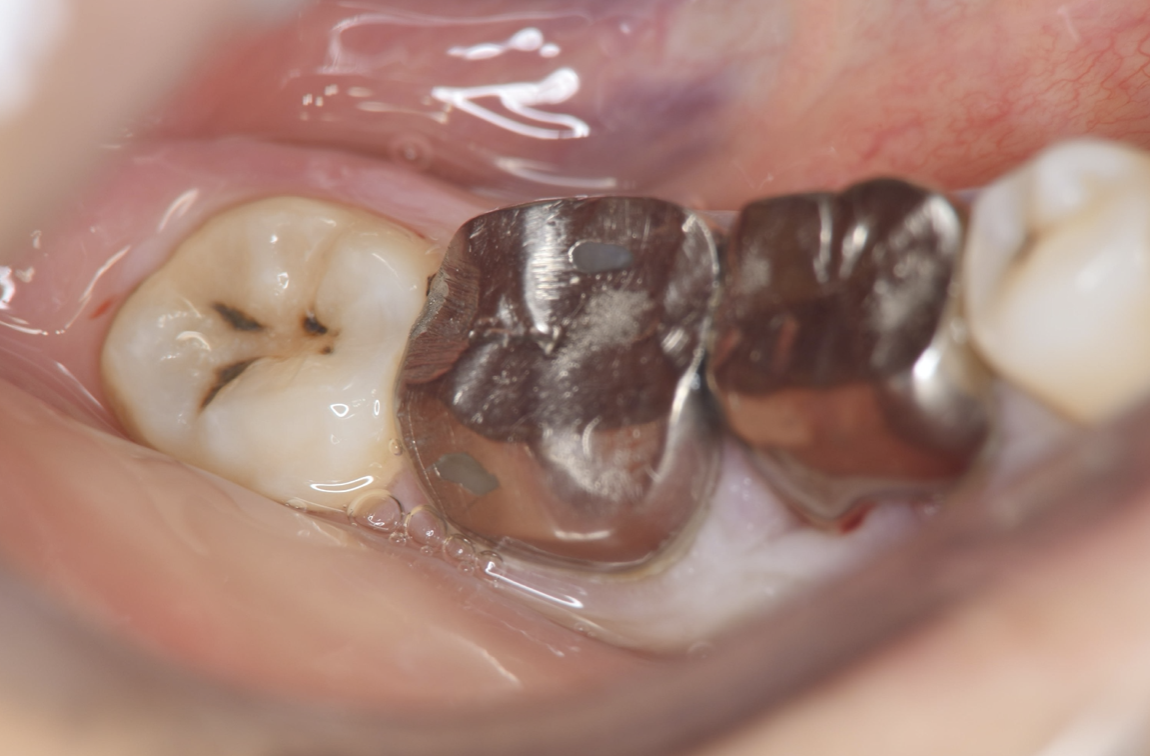

Figure 3.Preoperative intraoral findings. A metal crown was inserted at #46 and bleeding on probing during the periodontal pocket examination was noted.